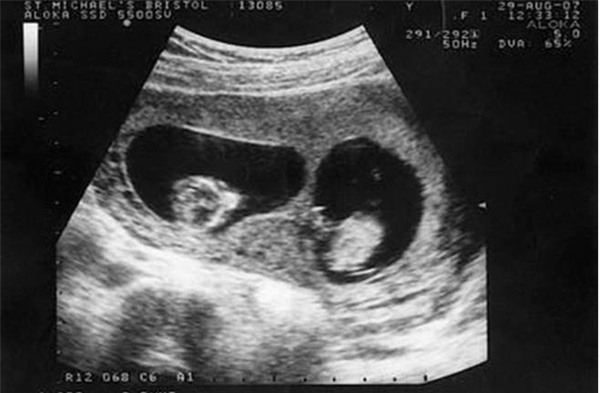

Trong thời kì đầu mang thai, Tiểu Mai, 25 tuổi, người Trung Quốc đi siêu âm và bác sĩ thông báo cô đang mang trong mình thai sinh đôi.

Trên thực tế, Tiểu Mai đã mang thai 3 đứa trẻ, 2 trai 1 gái nhưng khi siêu âm bác sĩ không hề thấy sự hiện diện của đứa trẻ thứ ba nên đã tiết lộ kết quả là sinh đôi.

Họ cũng cho biết, có thể 2 đứa bé kia đã nằm chắn đứa bé này nên khi siêu âm không nhìn thấy được.